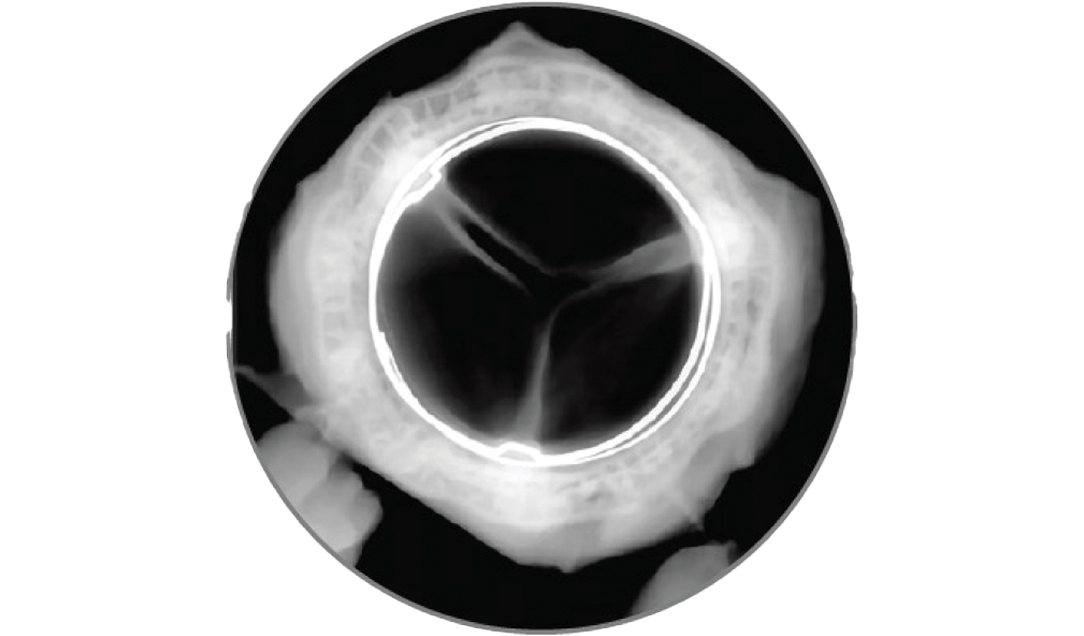

Since 2004, RESILIA tissue has been extensively studied. The growing body of clinical evidence supports RESILIA tissue valves' hemodynamic performance and resistance to structural valve deterioration in the mitral position.1,2

Clinically stable hemodynamics and one incident of structural valve deterioration (SVD) through 5 years.

Reduced calcification after 8 months, exceeding the 5-month reporting requirement